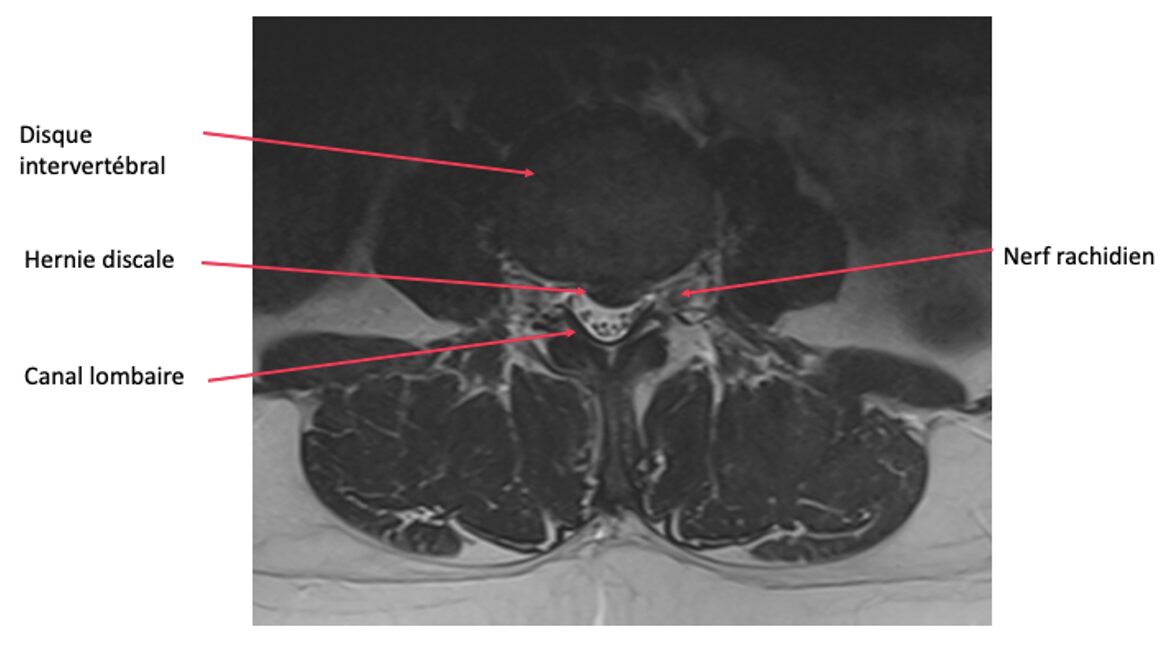

Figure 1. Hernie discale lombaire

La colonne vertébrale est composée d’une superposition de vertèbres. Entre chaque vertèbres se trouve le disque intervertébral, qui sert d’amortisseur, et qui est composé du noyau central et de « l’annulus » (partie périphérique). Lorsque l’annulus se déchire (souvent par usure)  une partie du noyau s’échappe : c’est que l’on appelle une hernie discale. Cette hernie peut comprimer un nerf à l’intérieur du canal vertébral.